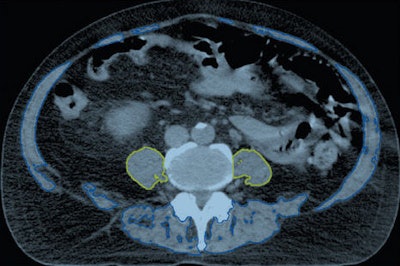

Axial CT images obtained in a 71-year-old man. Above, the bilateral psoas muscles (yellow) and total muscle area (blue and yellow) are delineated. Below, the vertebral body trabecular bone (green) is delineated. Images republished with permission from RSNA.Using CT performed for prostate cancer treatment planning, the researchers estimated bone mineral density at the mid-L5 level, specifically the mean CT attenuation in Hounsfield units of the trabecular bone of the L5 vertebral body, to generate a value they called L5HU. The second value, height-normalized psoas cross-sectional area, was called PsoasL4-5. The CT images were analyzed using Eclipse software (Varian Medical Systems).